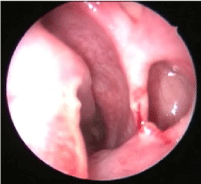

His general physical examination and systemic examination was normal. Ophthalmology evaluation was done, vision and ocular movements were found to be normal. He had 2 mm of enophthalmos and 4 mm of hypoglobus. Anterior rhinoscopy and diagnostic nasal endoscopy revealed a septal spur on the left side with normal pink nasal mucosa. Non contrast CT PNS was done, which showed a relatively small left maxillary sinus with inward retraction of the walls. Floor of the orbit and anterolateral walls were seen to have thinned out with resulting increase in the orbital volume causing hypoglobus (Figure 1A and Figure 1B). There was lateralization of the left uncinate process with obstruction of left osteomeatal complex. Complete opacification of left maxillary sinus was seen. The rest of the paranasal sinuses were normal. A diagnosis of Silent Sinus Syndrome was made.

Figure 1: A,B) CT PNS coronal section and axial section showing small maxillary sinus on the left side, with inward retraction of the walls and thinned out bone of the sinus with hypoglobus and opacification of the sinus. View Figure 1